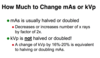

T/F: An overexposed radiograph is too light

False

An overexposed radiograph is too dark. Either kVp or mAs is too high.